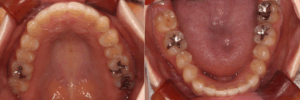

before

after

〈年齢・性別〉30代 女性

〈主訴・相談内容〉歯がガタガタしていて磨きにくいのと、かみ合わせが深くて下の歯が見えないのがずっと気になってました。

〈診断名〉叢生・過蓋咬合

〈装置〉インビザライン(コンプリヘンシブ)

〈抜歯部位〉非抜歯

〈治療期間〉1年3か月

〈治療費〉830,000円(税別・精密検査代込)